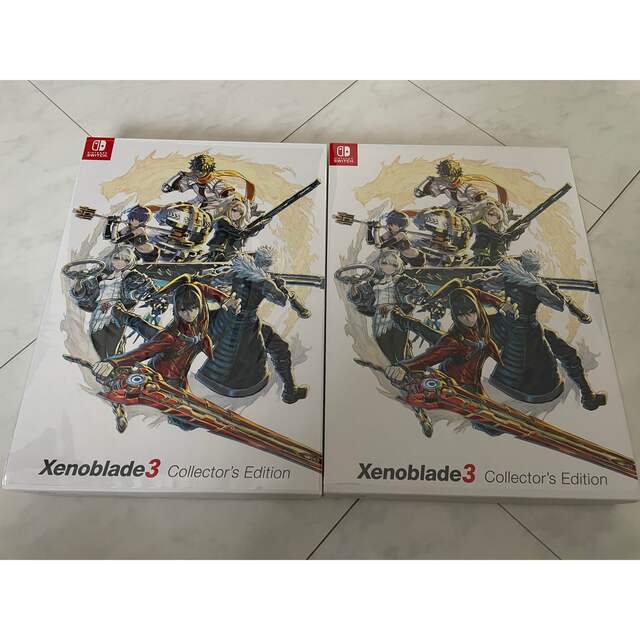

Thyroid Cancer Explore vol.3 no.2(2201 「Thyroid Cancer Expl Thyroid Cancer Treatment (PDQ®) - NCIの詳細情報

Thyroid Cancer Treatment (PDQ®) - NCI。Comparative Analysis of Metastatic Thyroid Carcinoma versus。The Role of Positron Emission Tomography/Computed Tomography。

ThyroidCancerExploreVol.3No

「ThyroidCancerExpl

Thyroid Cancer - Endotext - NCBI Bookshelf

Thyroid Cancer - Endotext - NCBI Bookshelf

■商品名■

ThyroidCancerExploreVol.3No

「ThyroidCancerExpl